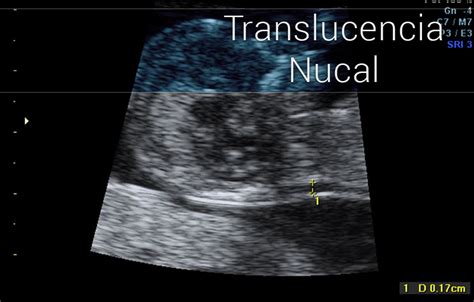

- Evaluar la Translucencia Nucal: La medida del espacio con líquido linfático en la nuca del feto, un indicador de posibles alteraciones cromosómicas.

La medición de la translucencia nucal, combinada con la edad materna y los factores bioquímicos del cribado combinado, permite obtener un índice de riesgo de alteraciones cromosómicas frecuentes, como el Síndrome de Down (trisomía 21) y el Síndrome de Edwards (trisomía 18).